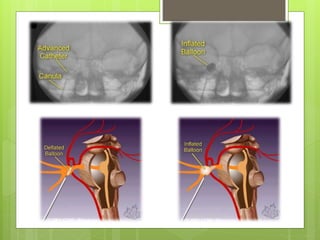

(C) Percutaneous balloon compression:

introduced by Mullan & Lichtor in 1980.

Technique:

A no. 4 Fogarthy’s catheter is introduced with

fluoroscopic guidance.

A 0.7 mm balloon is inflated for 1 – 2 minutes.

(C) Percutaneous ballooncompression: This is a mechanical means of destruction of the trigeminal nerve introduced by Mullan & Lichtor in 1980. Technique: A no. 4 Fogarthy’s catheter is introduced with fluoroscopic guidance. A 0.7 mm balloon is inflated for 1 – 2 minutes.